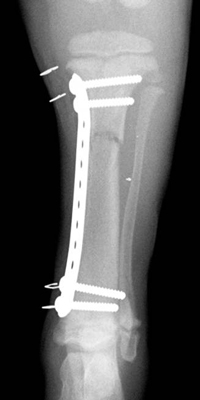

ü Try the new kid on the block. Loïc Déjardin, a board-certified surgeon at Michigan State University, has been investigating a very elegant technique borrowed from human surgery. It is called elastic plate osteosynthesis, or minimally invasive plate osteosynthesis, or else biological osteosynthesis. It seems like an ideal compromise to repair a bone with a plate while being both a carpenter and a gardener.

Once the main bone fragments are realigned using one of the techniques described above, a small skin incision is made proximally and one distally. A long bone plate is slipped through a tunnel between the soft tissues and the periosteum. The plate is then secured to the bone with a couple of screws proximally and distally.